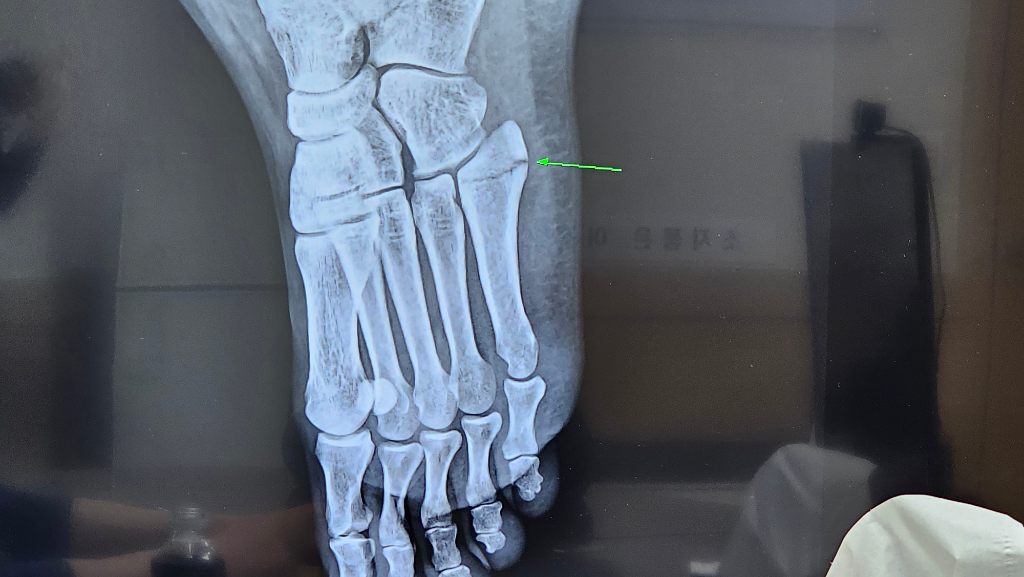

중족골5번 엑스레이 금간게 어디까지인지?

제가 길을 걷다 발을 헛디뎌서 왼쪽발 중족골5번 금이 갔는데요. 끝쪽만인건지 저 미세한 선 그어진 그거까지도 금간건지 헷갈려서요. 의사쌤께서는 끝쪽만이라는데 주변에서는 5번 선 그어진 부분 다 금간거 아니냐고해서요, 이게 엑스레이 다른 뼈랑 겹쳐서 선이 생긴건지 아님 진짜 끝쪽만인건지 궁금해서요. 현재 4주차이고요. 1주차때보다 희한하거 더 벌어진거 같고, 의사쌤도 당황하셨지만 어쨌든 사진 보시고 알려주세요

말씀하신 5번 중족골 골절은 끝쪽만 금이 간 경우가 많고 엑스레이에서 보이는 선이나 다른뼈나 혈관 그림자일 수도 있습니다. 다만 선이 더 벌어진 듯 보이고 의사도 당황했다면 골절이 진행되었거나 불안정한 상태일 가능성도 있습니다 정확한 판단은 엑스레이 판독 경험이 있는 전문의가 해야 하고 필요하면 ct나 mri를 추가로 촬영하는 것이 좋습니다!

두번째 사진을 보면 중족골 base에 골절선이 길게 이어져 있는 것을 확인할 수 있습니다

첫번 째 사진보다는 훨씬 뚜렷하게 보이는 것 같습니다